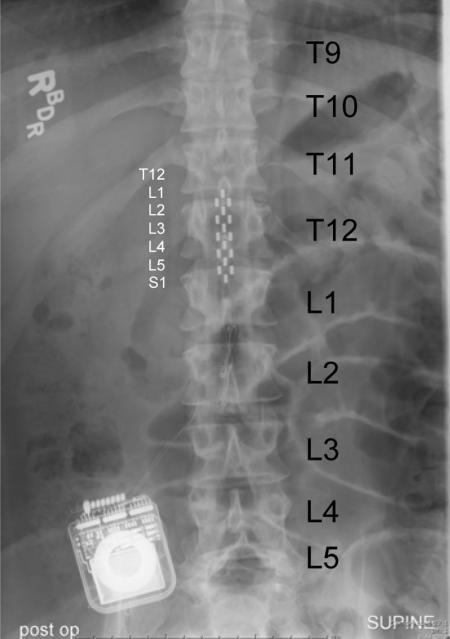

Joel W. Burdick, Richard L. and Dorothy M. Hayman Professor of Mechanical Engineering and Bioengineering, and Yu-Chong Tai, Professor of Electrical Engineering and Mechanical Engineering, are developing new technologies to expand their research which has enabled a paraplegic man to stand and move his legs voluntarily. The team has until now used intelligent guesswork to determine which stimuli might work best. But soon, using a new algorithm developed by Professor Burdick, they will be able to rely on a computer to determine the optimum stimulation levels, based on the patient's response to previous stimuli. This would allow patients to go home after the extensive rehab process with a system that could be continually adjusted by computer. [Caltech Release] [ENGenious Progress Report]